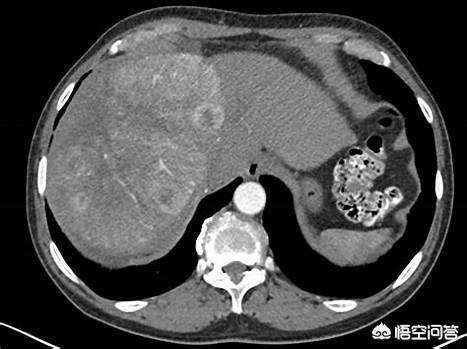

この症例は55歳の慢性B型肝炎患者である。健康診断の超音波検査で肝占有、AFP上昇、画像検査でごく典型的な肝癌を認めた。B型肝炎に罹患している場合は、定期的な検診を受けることが重要です!

CTでは、典型的な肝細胞癌が写っている。速いイン、速いアウトその顕在化を見るには、強化検査をしなければならない。このような結節を見れば、肝がんと診断する自信はある。また、肝細胞癌は病理学的に確定診断がなくても治療が可能な唯一の疾患であり、画像診断での典型性とB型肝炎の既往に基づいて診断される。